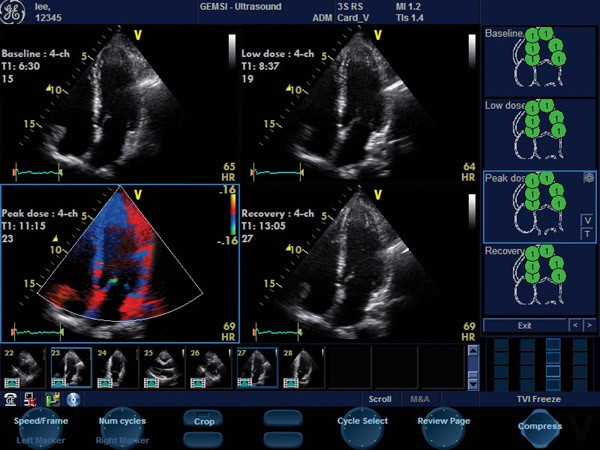

Próba dobutaminowa to uznana, zasadniczo bezpieczna i nieinwazyjna metoda diagnostyczna, polegająca na monitorowaniu pracy serca za pomocą echokardiografu przy stopniowo zwiększanym obciążeniu lekiem – dobutaminą.

Celem próby dobutaminowej jest kontrolowana ocena ewentualnego niedokrwienia mięśnia sercowego oraz określenie stopnia uszkodzenia, które może wskazywać na chorobę wieńcową, jej zaawansowanie oraz potrzebę dalszej diagnostyki, w tym wykonania koronarografii.

Echokardiografia dobutaminowa u pacjentów po zawale serca ma również dużą wartość w ocenie żywotności określonych obszarów mięśnia sercowego oraz w prognozowaniu powrotu funkcji skurczowej lewej komory u osób leczonych pierwotną angioplastyką (PCI) lub pomostowaniem naczyń wieńcowych (CABG).

W naszym ośrodku wykonujemy badanie echo serca aparatem Vivid S 5.